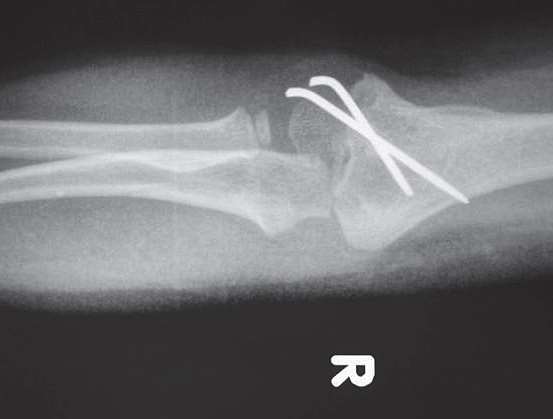

3.影像学检查(图7-1)。

图7-1 肱骨髁骨折X线片